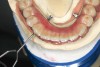

Fig 9. Intraoral view of the titanium bridge framework with individual lithium-disilicate crowns.

Figure 9